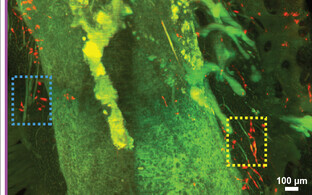

Nii õnnestuski Sestani töörühmal taastada enne aju surma selles vereringe. Hapnik jõudis taas tehisverest, pumpadest ja soojendajatest koosneva süsteemi BrainEx abil ajurakkudeni, misläbi jäid miljardid rakud pealtnäha täiesti terveks.

Sestan märkis, et töörühma eesmärk polnud aju pikaajaline säilitamine ega ettevalmistuste tegemine ajusiirdamiseks. Selle asemele loodab ta kollegidega edendada sellega alusteadusi. Võimalus uurida tervet inimaju pikema aja vältel aitaks Sestani sõnul paremini mõista näiteks koomat, dementsust ja teisi närvihaigusi ning töötada välja teraapiaid ka vähipatsientide aitamiseks. Eeskätt loodab ta kolleegidega luua ajurakkude omavahelisi ühendusi kaardistava atlase.